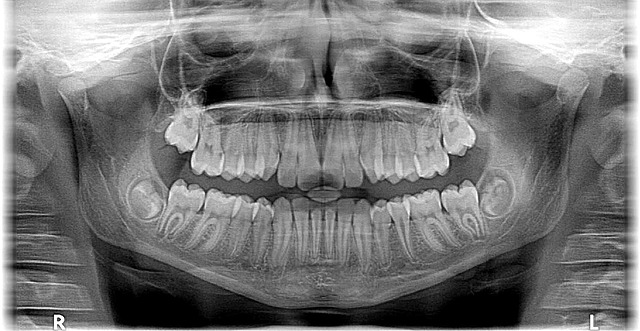

The process typically starts with a comprehensive consultation where the orthodontist mcallen examines the patient’s mouth, takes X-rays, and discusses their concerns. They may recommend jaw surgery, particularly if traditional orthodontic treatments have not provided the desired results. This decision is based on extensive knowledge of skeletal and dental anomalies. Once approved, patients often work closely with the orthodontist throughout the treatment plan, which can include a combination of braces and other devices to prepare the jaws for surgery.